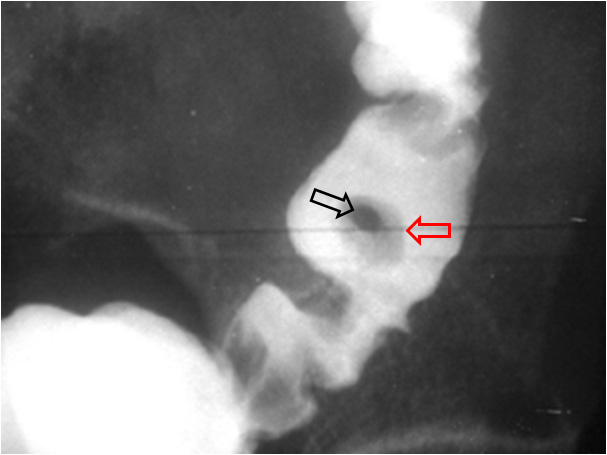

SIGNO DEL SANDWICH

Signo de linfoma abdominal tanto en la TC como en ecografía. Consiste en la presencia de masas adenopáticas que rodean y desplazan la arteria y la vena mesentéricas superiores sin comprimirlas.

La fotografía corresponde a un paciente con linfoma (flecha roja) que forma conglomerados adenopáticos que respetan los vasos mesentéricos (flecha blanca).

Por extensión, se puede emplear este signo en conglomerados linfomatosos que rodean pero respetan otras estructuras vasculares diferentes de los vasos mesentéricos, como vemos en el ejemplo siguiente con las arterias renales.

Imagen tomada, con permiso del autor de la web https://radiodiagnosticando.com/2014/06/17/caso-signo-de-la-aorta-flotante/